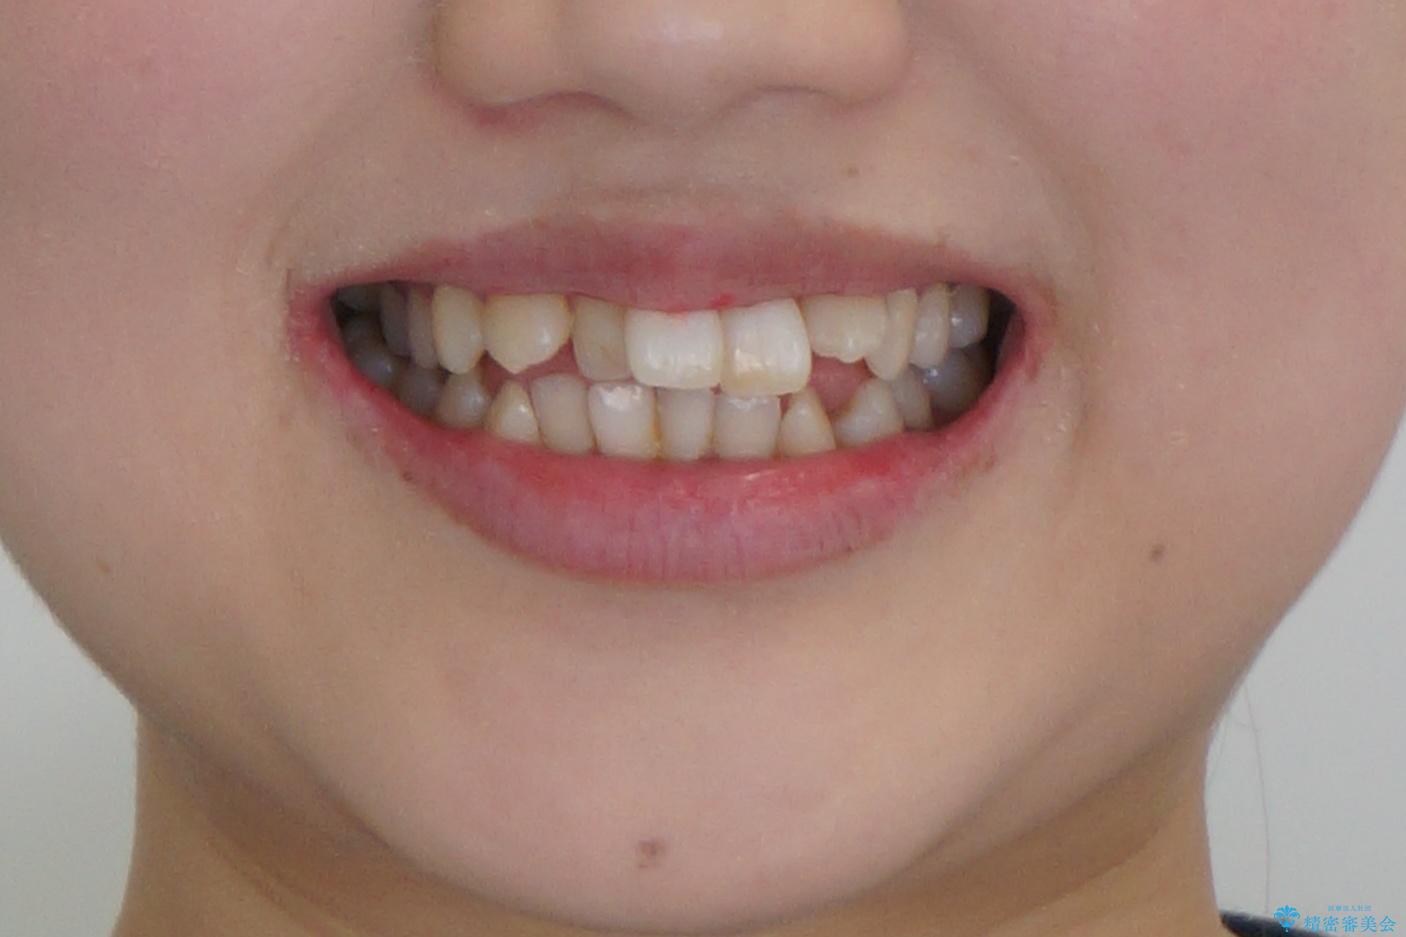

難症例 奥歯がかみ合っていない 歯並び矯正で別人に

- 歯並びを気にして来院。

前歯は重度のがたつき、また奥歯はすれ違っていました。

治療は3年以上かかりそうと説明しましたが、2年台で終わらせることができました。

上下左右4本抜歯の可能性を説明していましたが、実際は上顎2本の小臼歯抜歯で済みました。

矯正用インプラントを使用して治療しています。

上下の顎の幅もあっておらず、成人でしたが手術なしで上あごを骨から広げる処置(急速拡大装置)を行いました。